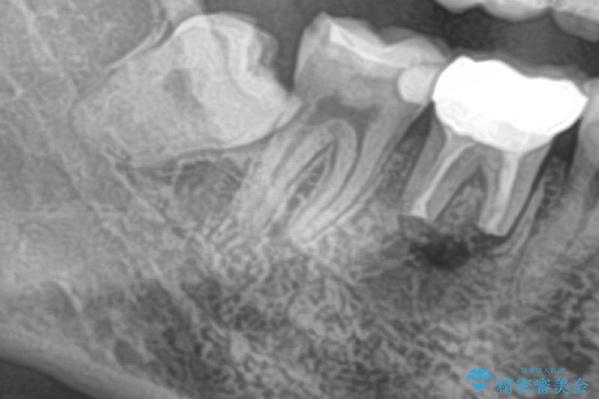

- 右下の親知らずを抜きたいとのことで来院された患者様です。

CTで神経の位置などを確認し、抜歯術を行いました。